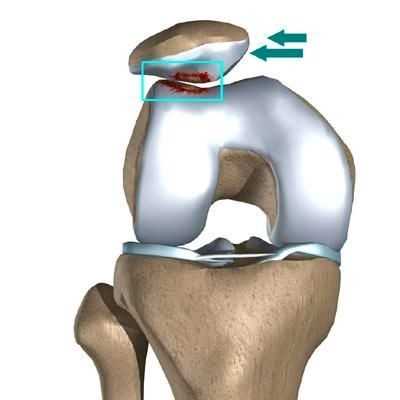

в) При вывихе надколенника медиальная фасетка ударяется о дистальную часть наружного гребня блока мыщелка бедра, что нередко приводит к хондральному или остеохондральному повреждению в этой области и классической МР-картине костных кровоизлияний.

Латеральный вывих надколенника характеризуется разрывом медиального ретинакулюма (медиальной пателло-феморальной связки) коленного сустава. Повторный вывих у пациента — главный признак не выполнения медиальной пателло-феморальной связкой своих функций из-за перерастяжения после первичной травмы.

Вывих надколенника, как первичный, так и повторный, ведет к значимому повреждению хрящевого покрова. Как результат — появляется стойкий болевой синдром и снижение физической активности пациента.